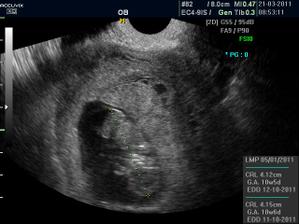

Pidižva č.2 a č.3... :o)